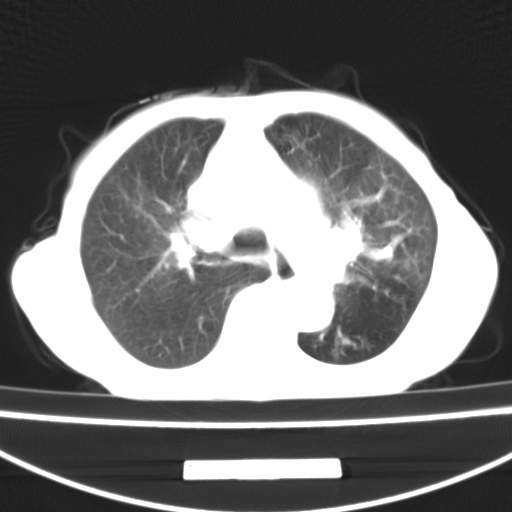

患者 女 67岁,反复咳嗽咳痰2年,加重伴喘及双下肢浮肿1月

诸大血管及f肺门血管增粗迂曲.左下肺多发薄壁空腔影.部分非也透亮度增高.薄曾扫描可区分肺气肿类型.考虑1.慢性支气管炎 2.左下肺支气管扩张 3.肺气肿 4 肺动脉高压5.是否有先心病病史

考虑1.慢性支气管炎 2.左下肺支气管扩张 3.肺气肿 4 肺动脉高压

慢支炎、肺气肿、双肺感染、左下囊状支扩。

慢支、肺气肿、肺动脉高压;左下肺囊状支扩并粘液栓形成。